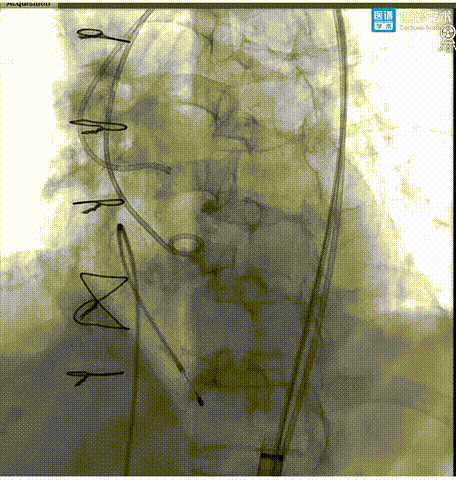

8. 第三次释放后,超声、造影评估示瓣膜植入深度、工作形态良好、微量瓣周漏,交换猪尾导管测的平均跨瓣压差2mmHg,手术圆满成功。